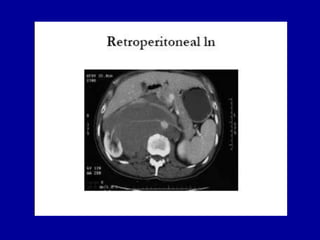

ESTUDIOS DE IMAGENTAC de alta resolución de abdomen y pelvisRx tórax PAMetástasis ganglionares aparecen inicialmente en ganglios linfáticos retroperitonealesAunque TAC es la modalidad de elección para evaluar retroperitoneo, se ha descrito una tasa de falsos negativos tan altos como del 40%

ESTUDIOS DE IMAGENTACde alta resolución de abdomen y pelvisRx tórax PAMetástasis ganglionares aparecen inicialmente en ganglios linfáticos retroperitonealesAunque TAC es la modalidad de elección para evaluar retroperitoneo, se ha descrito una tasa de falsos negativos tan altos como del 40%